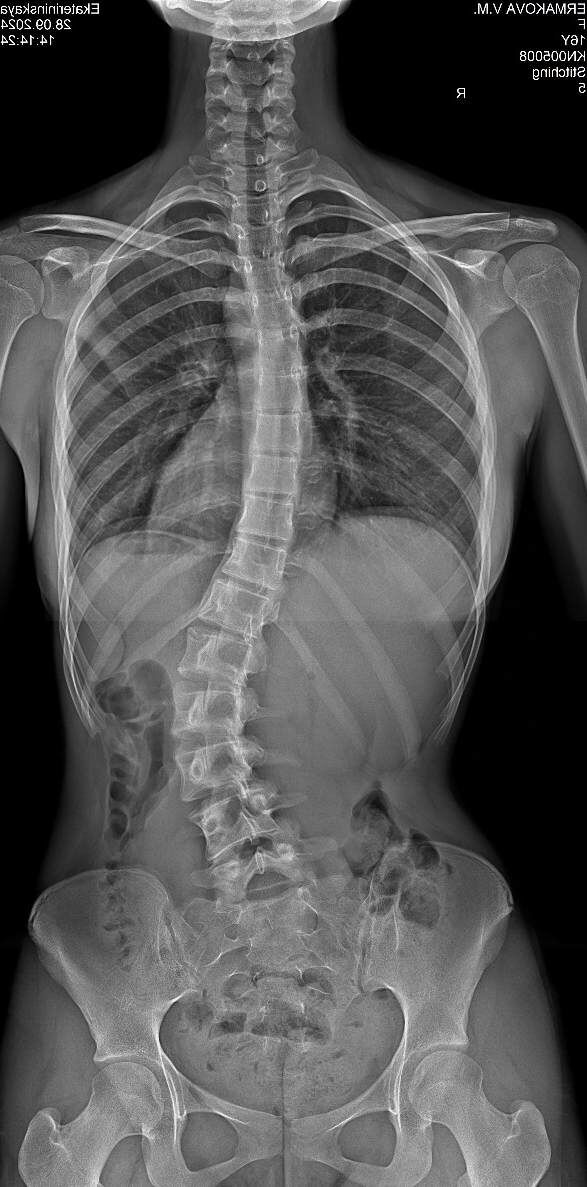

Вот последний снимок до ношения корсета:

В итоге сейчас позвоночник в корсете с углом искривления 10 градусов! Считаю это успехом. Результаты впечатляют, но радоваться пока рано, ведь может быть и сильный откат после снятия корсета Шено. Ну и наша задача победить ещё 5 градусов и можно закачивать мышцы.

Лера стала чувствовать себя увереннее, осанка заметно улучшилась, спина визуально выглядит эстетичнее. Конечно, путь к полному выздоровлению еще долгий, но мы видим положительную динамику.